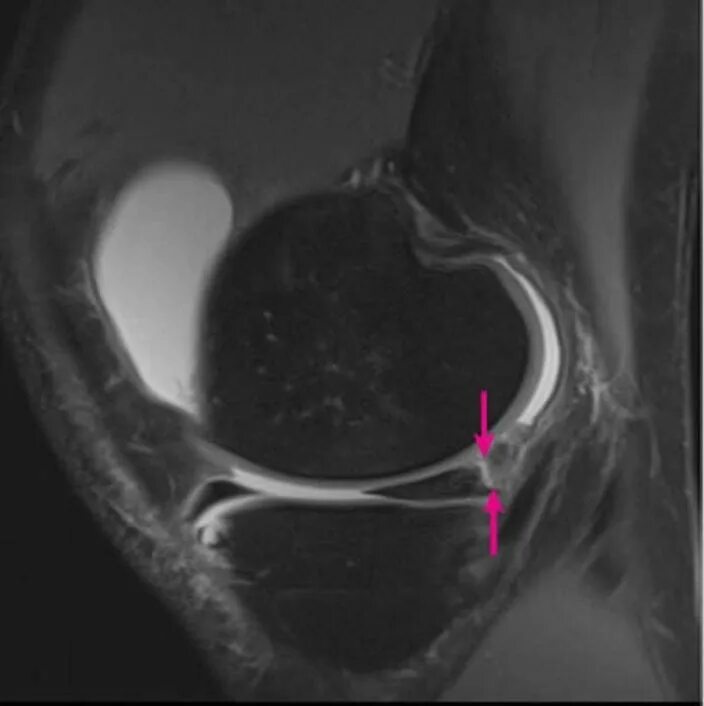

Повреждение мениска мрт